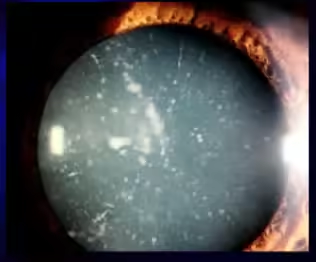

Tipos de catarata

- Catarata congênita: presente no nascimento, por causa genética ou problemas durante a gestação. É uma das causas tratáveis de cegueira na infância.